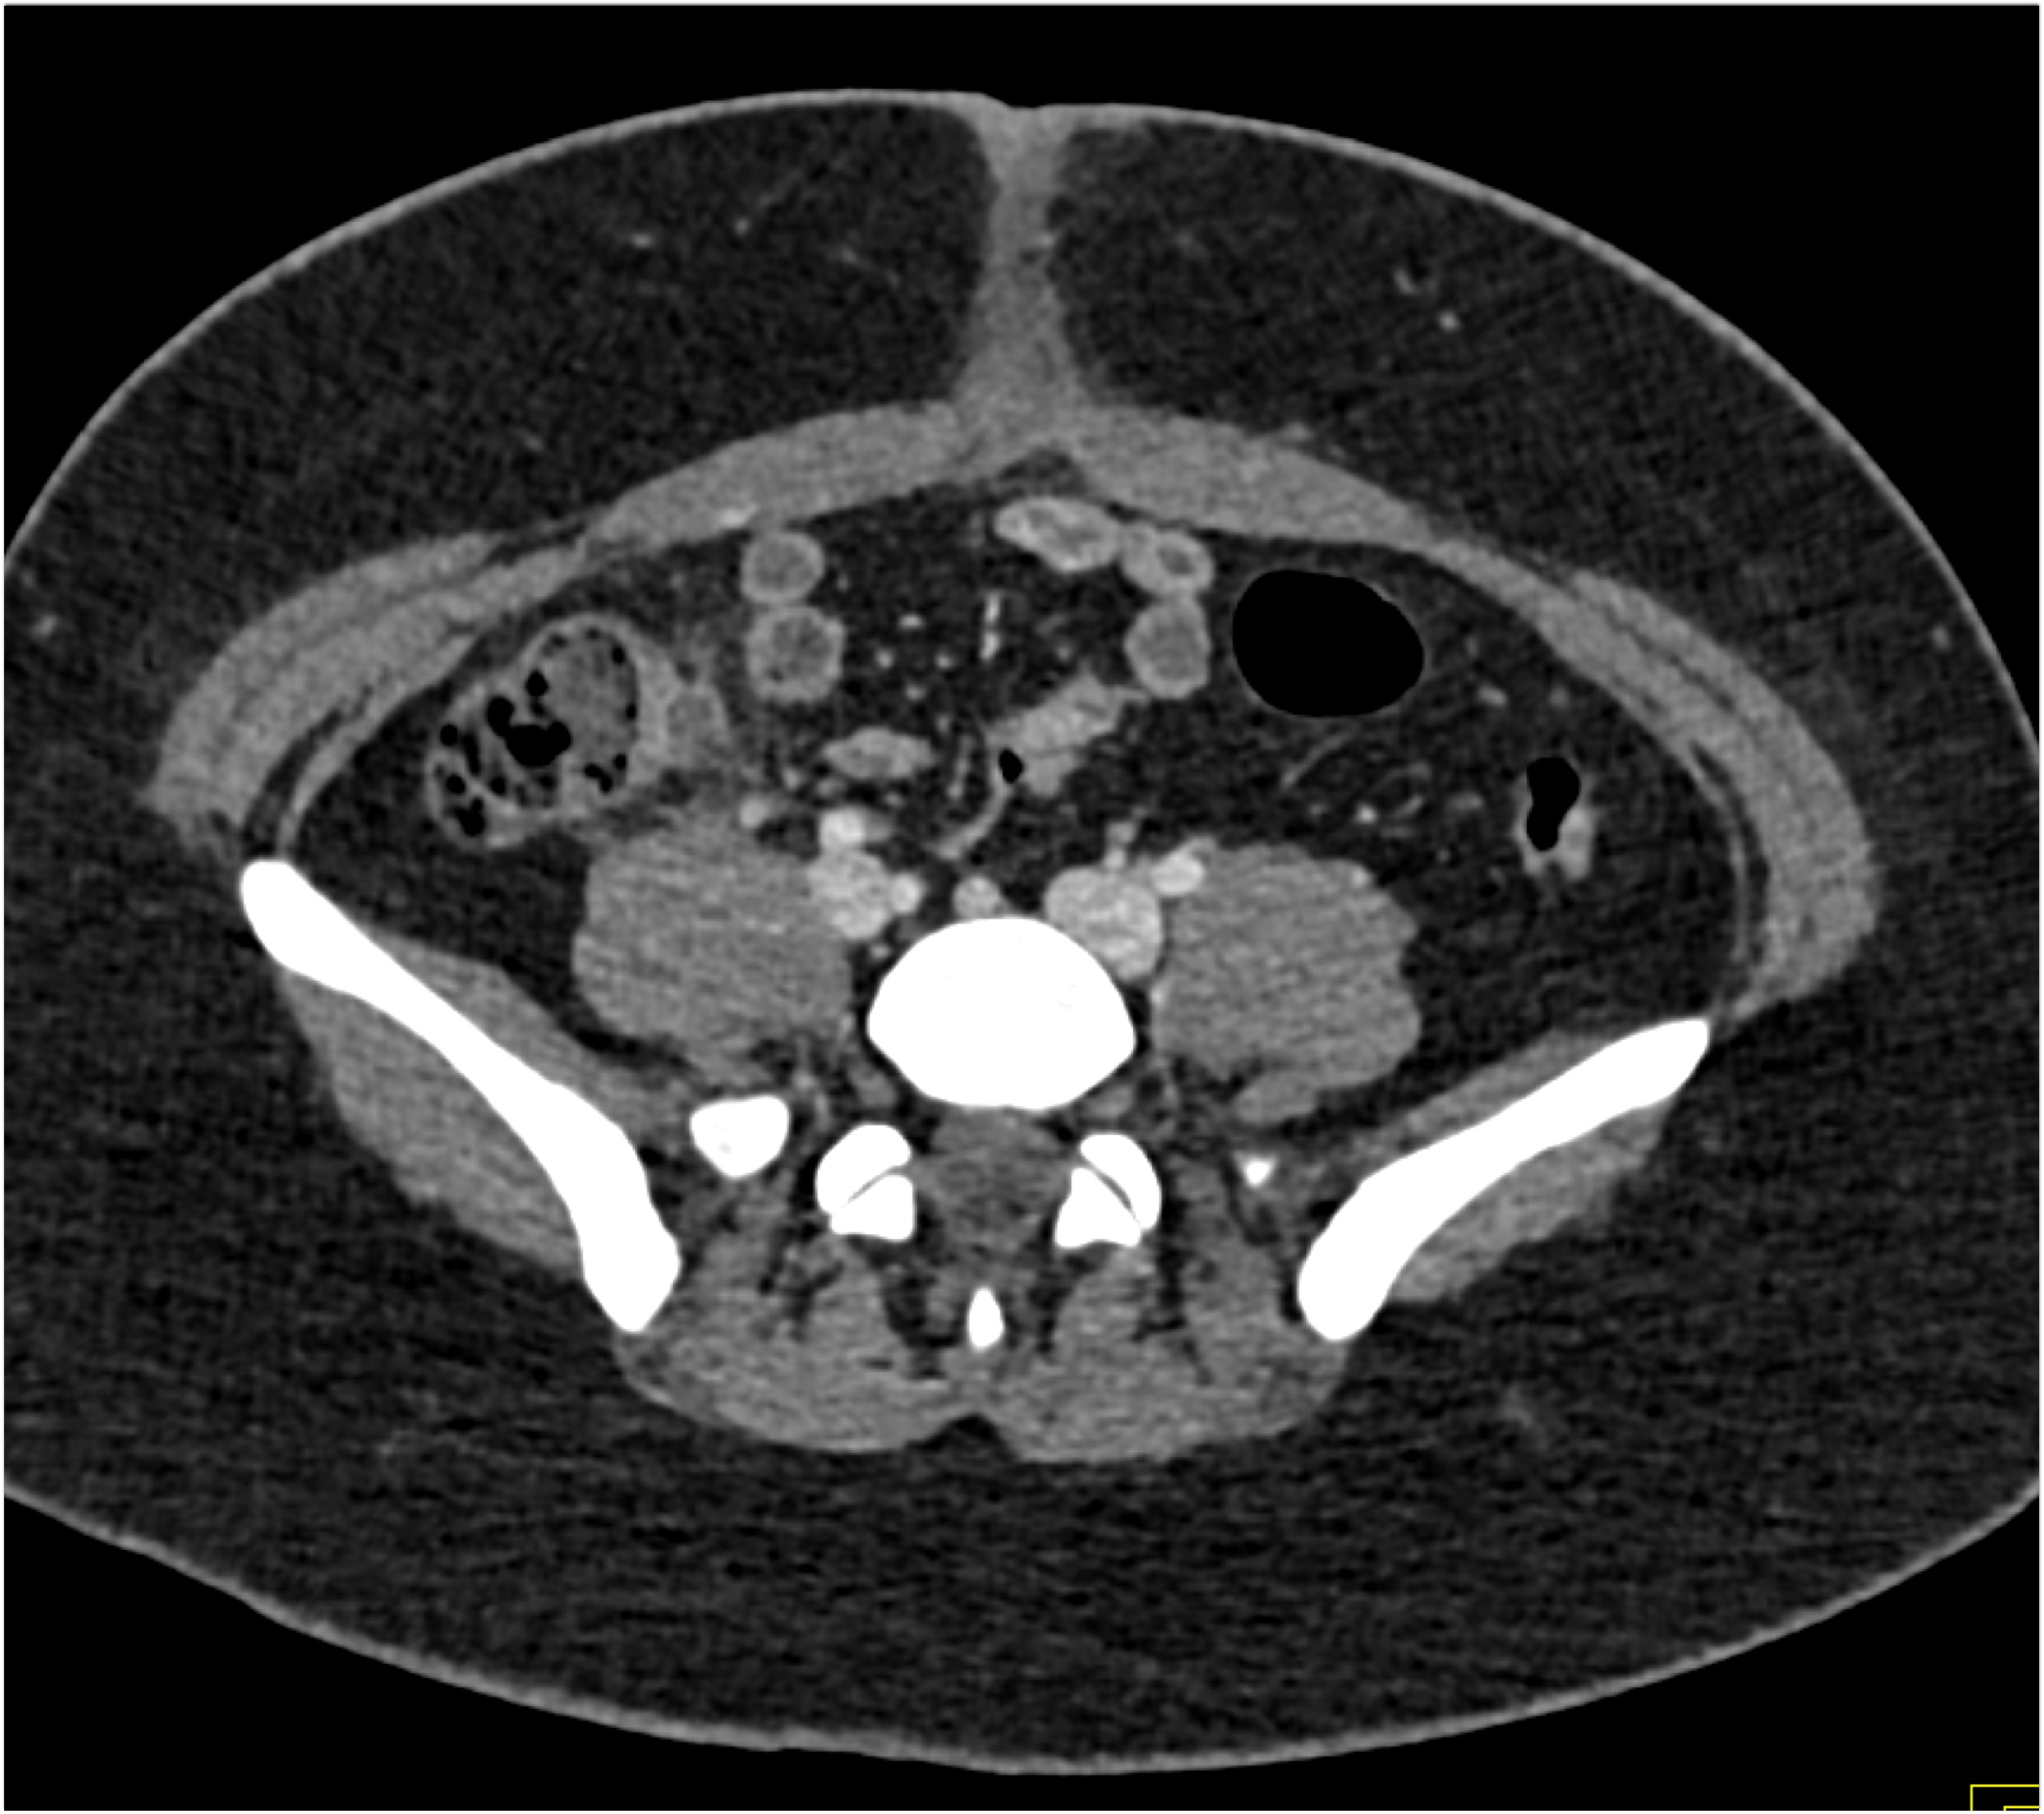

9) The best diagnosis in this 30ish year old female is?

renal cell carcinoma

MEST tumor (mixed epithelial and stromal tumor)

Wilms tumor

polycystic kidney disease